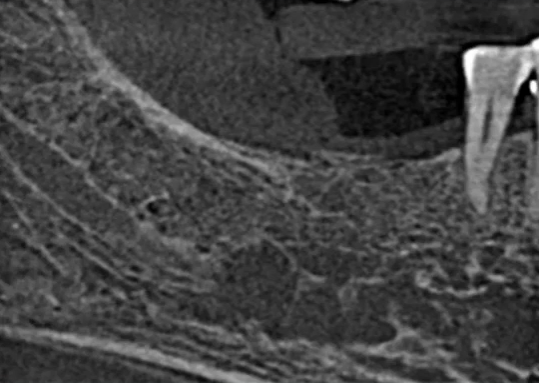

根尖片进一步诊断

47龋坏伴根尖炎

曲面断层片怎么看口腔精读 | 一次性教你看懂曲面断层片!_https://www.jmylbn.com_新闻资讯_第54张

曲面断层片怎么看口腔精读 | 一次性教你看懂曲面断层片!_https://www.jmylbn.com_新闻资讯_第55张

37继发龋!根尖炎?

曲面断层片怎么看口腔精读 | 一次性教你看懂曲面断层片!_https://www.jmylbn.com_新闻资讯_第56张

曲面断层片怎么看口腔精读 | 一次性教你看懂曲面断层片!_https://www.jmylbn.com_新闻资讯_第57张

25远中邻面浅龋

曲面断层片怎么看口腔精读 | 一次性教你看懂曲面断层片!_https://www.jmylbn.com_新闻资讯_第58张

曲面断层片怎么看口腔精读 | 一次性教你看懂曲面断层片!_https://www.jmylbn.com_新闻资讯_第59张